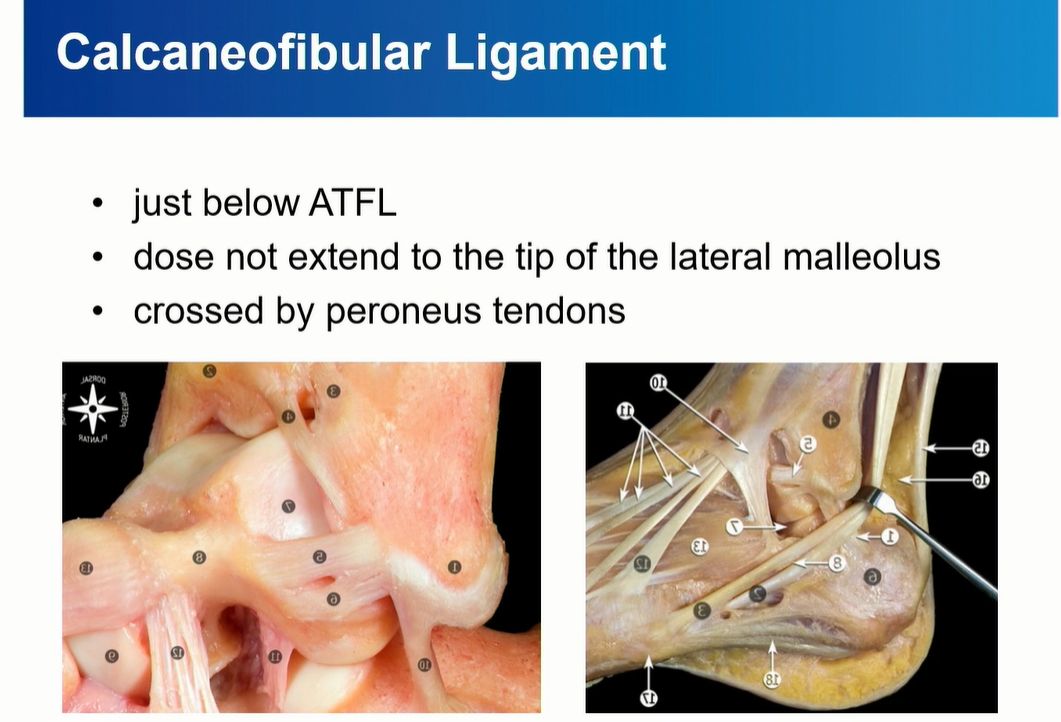

2-2 . CFL (Calcaneofibular ligament)

ATFL과 떨어져서 기시한다는 이야기도 있었지만, Just below ATFL로 이해하면 좋을 것 같다.

Peroneal tendon을 landmark로 이용해서 CFL를 찾는 것도 연습해야 함.

Axial cut과 coronal cut에서 모두 확인할 수 있는데, Axial cut의 경우에는 peroneal tendon 내부에 위치한 것을 확인할 수 있다.